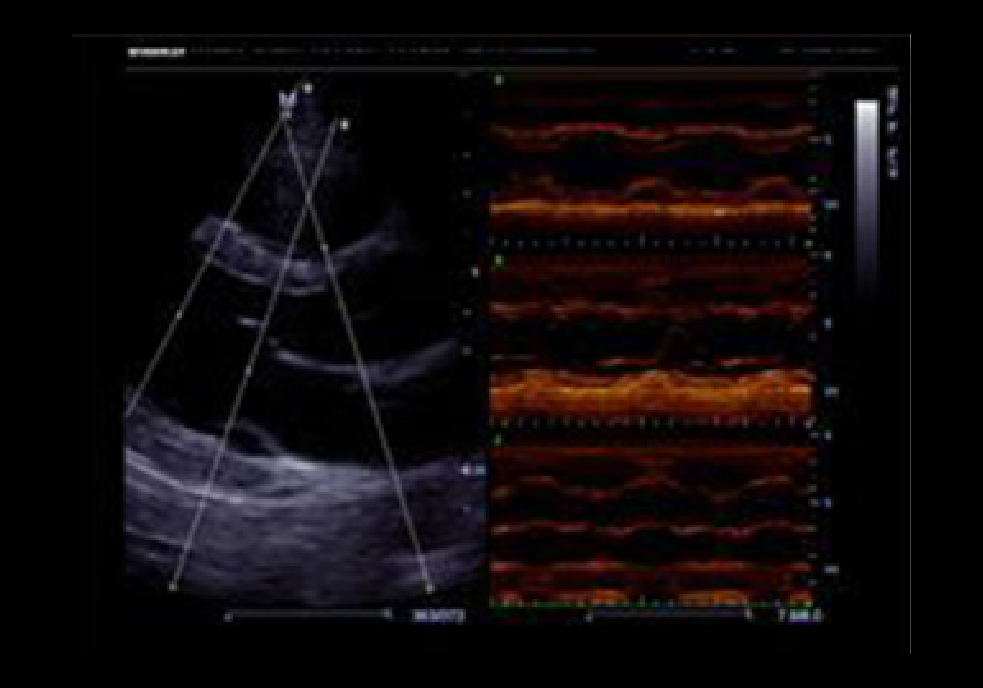

Free Xros MTM

Gain precise anatomical observation by freely placing sample lines at any angle. Attain better images through simultaneous display of up to 3 sample lines.